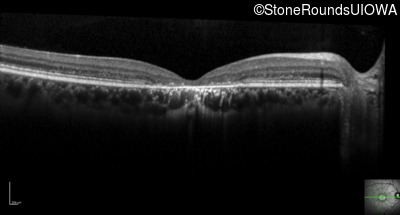

Optical Coherence Tomography - Right - 20/125

Exemplar / OCT Stack

Optical Coherence Tomography - Left - 20/125